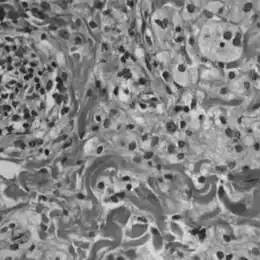

Histologie

La maladie de Chester-Erdheim se distingue de l'histiocytose langerhansienne sur plusieurs points :

• elle n'est pas mise en évidence, contrairement à l'histiocytose langerhansienne, par un marquage à la protéine S-100 ou au CD 1a[13]

• une analyse du cytoplasme en microscopie électronique ne révèle pas de granules de Birbeck[13]

• les échantillons tissulaires montrent des infiltrations xanthomateuses ou xanthogranulomateuses par des histiocytes spumeux (gorgés en graisses), dans un environnement habituellement fibrosé.